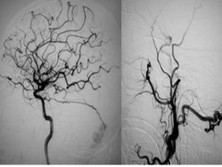

硬脑膜动静脉瘘

硬脑膜动静脉瘘(duralarteriovenousfistulas,DAVFs...

脑血管造影